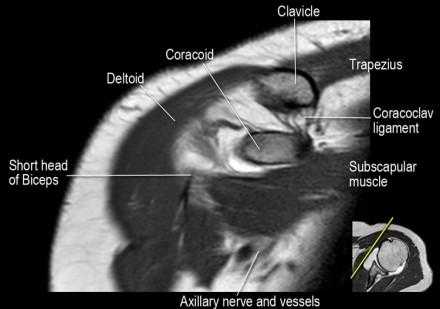

Нормальная корональная анатомия плечевого сустава и контрольный список

- обратите внимание на клюво-ключичную связку (coracoclavicular ligament) и короткую головку двуглавой мышцы (short head of the biceps).

- обратите внимание на клювоакромиальную связку (coracoacromial ligament).